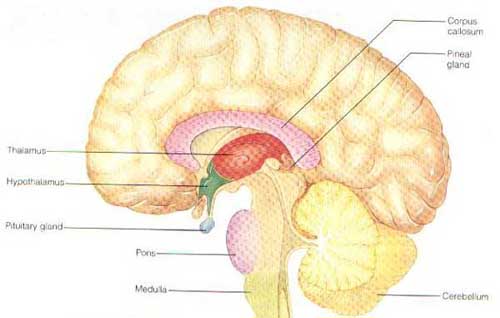

عجز العلماء عن معرفة هذه القوة الخارقة التي يمتلكها الإنسان بعد اندماج الروح بالجسد . ولايمر يوم من أيام الدنيا إلا والدراسات والاكتشافات العجيبة تخرج عن تلك القوى التي يمتلكها هذا العقل . ولما عكفوا على دراسة العقل لم يجدوا السر داخل المخ المرئي حتى بعد تشريحه وتصويره ومتابعته، فخلصوا إلى وجود عقل أكثر عمقا غير مرئي ولا ملموس ولا مسموع تنطلق منه أوامر الروح ، وأسموه بالعقل الباطن أو بالعقل اللاواعي .

الرسالة و يعدلها لكي نري الصورة بالمعدول . لكن الانسان له عين فزيائية أخري فائدتها ظلت غير معروفة للبشرية .

الرسالة و يعدلها لكي نري الصورة بالمعدول . لكن الانسان له عين فزيائية أخري فائدتها ظلت غير معروفة للبشرية .